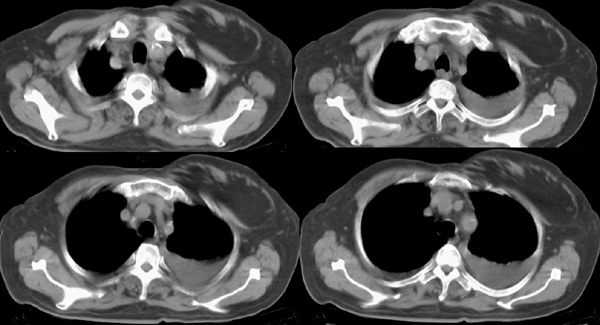

以下是引用panyishengct在2008-5-19 21:48:00的发言:[br]左侧胸壁脂肪瘤;肺部还是考虑肺水肿,胸腔积液。 [br] [br]左肺门见一团状影,纵隔见淋巴结,建议治疗后复查,以排外中央型肺癌

以下是引用形影不离在2008-5-19 21:13:00的发言:[br]左侧胸壁脂肪瘤;肺部还是考虑心衰并肺水肿,胸腔积液。